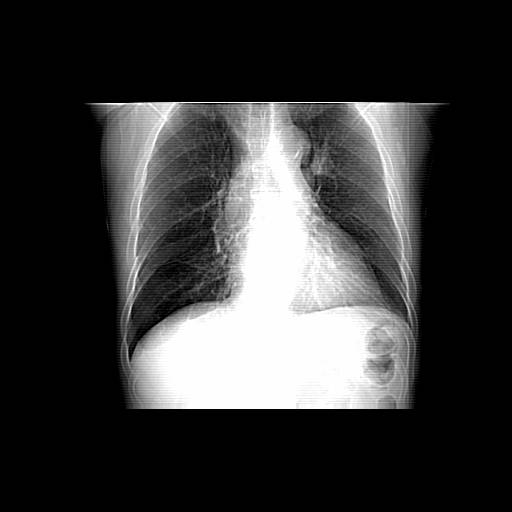

以下是引用zjzjr在2006-12-6 19:04:00的发言:[br]左肺上叶尖后段可见椭圆形高密度影,其内可见点状钙化影,周围可见卫星病灶.首先考虑结核,双侧少量胸腔积液.

以下是引用李世军在2006-12-6 19:54:00的发言:[br]左肺上叶尖后段可见椭圆形高密度影,其内可见点状钙化影,周围可见卫星病灶.首先考虑结核,双侧少量胸腔积液. [br] [br] 双肺轻度肺气肿,左肺上叶后段见多发斑片状密度增高影,周围见少许斑点状卫星病灶,双侧胸膜增厚粘连,纵隔内未见明显改变,考虑结核可能性大,请结合临床或增强扫描. [br] [br]

以下是引用13081830109在2006-12-6 19:35:00的发言:[br]左肺上叶尖后段可见椭圆形高密度影,其内可见点状钙化影,周围可见卫星病灶.首先考虑结核,双侧少量胸腔积液.

以下是引用守望可可西里在2006-12-7 0:01:00的发言:[br][quote]以下是引用zjzjr在2006-12-6 19:04:00的发言:[br]左肺上叶尖后段可见椭圆形高密度影,其内可见点状钙化影,周围可见卫星病灶.首先考虑结核,双侧少量胸腔积液.